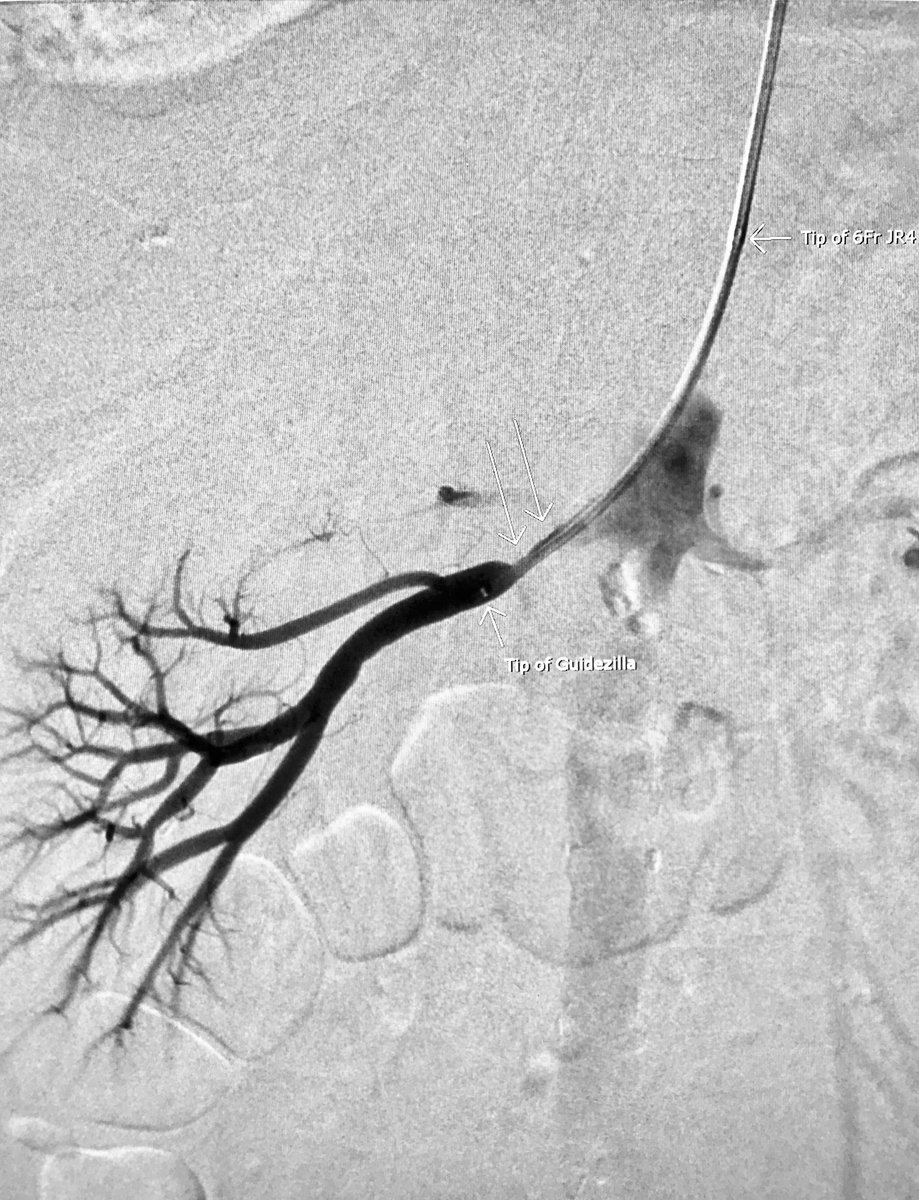

Significant R renal artery stenosis. @ThinkRadial stenting. 6Fr JR4 guide didn’t reach so borrowed #Guidezilla from cath lab for the win. #IRad #MIIP @SIRspecialists @SIRRFS

AlexCVIR's tweet image. Significant R renal artery stenosis. @ThinkRadial stenting. 6Fr JR4 guide didn’t reach so borrowed #Guidezilla from cath lab for the win. #IRad #MIIP @SIRspecialists @SIRRFS